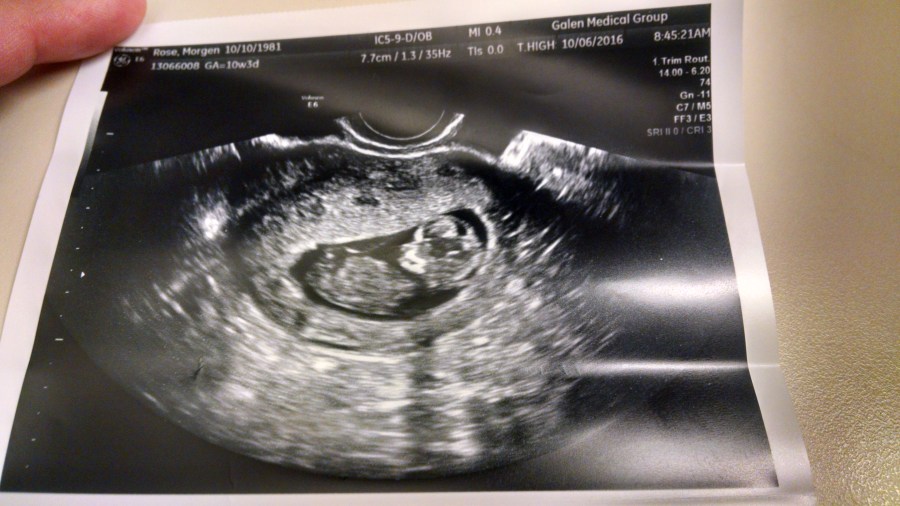

We did my third ultrasound and suddenly the blob that became a turtle has become a tiny person. Which is, again, weird. Heart rate looks good, everything is exactly the way it should be, so all news is good news.